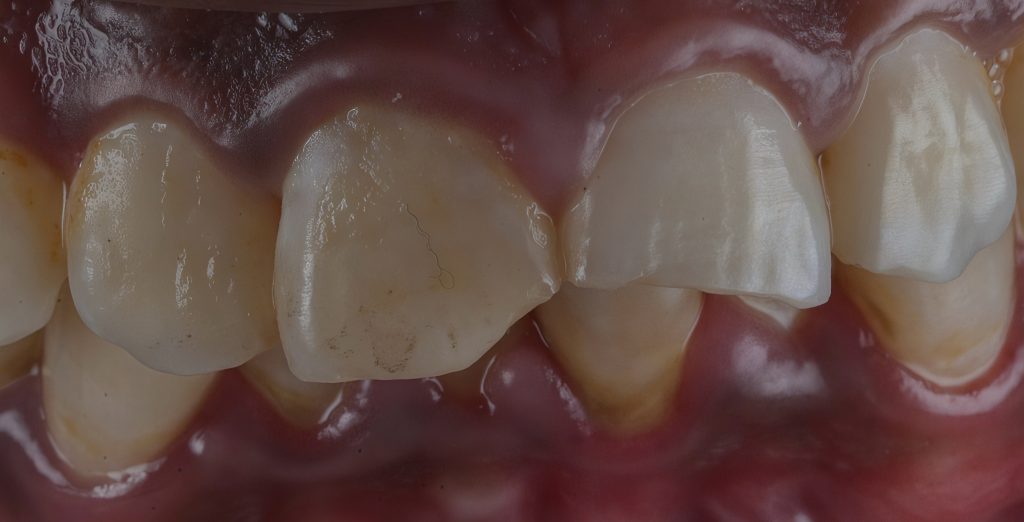

- Teeth involved: 11 and 21 (FDI system)

- Trauma history: uncomplicated enamel–dentine fracture

Post-traumatic enamel–dentine fracture with aesthetic impairment.

STEP 3 – Silica Index and Palatal Shell Fabrication

A 3D smile mock-up was designed and approved by the patient to define final tooth proportions and width-to-length ratios. A silicone putty index was fabricated from the mock-up to create a palatal shell. This shell provided a stable incisal edge position and guided functional envelope during reconstruction. (Fig.3)